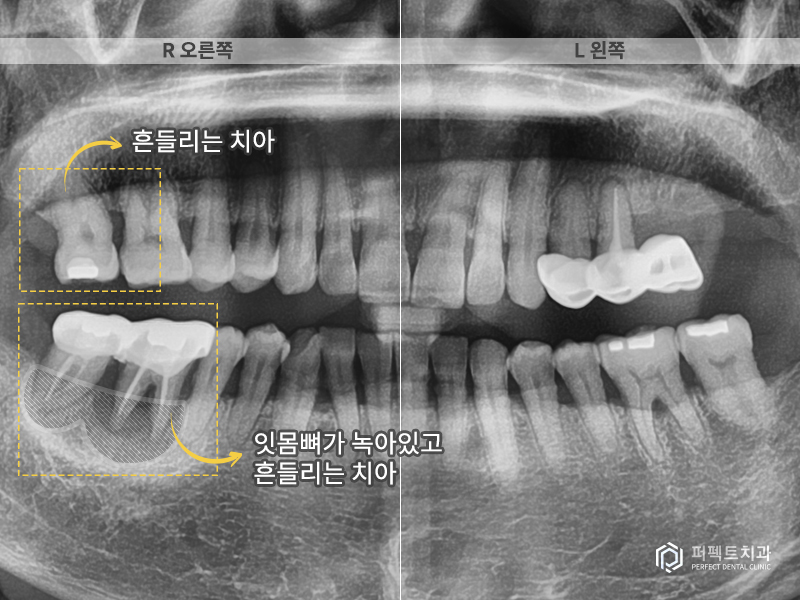

첫 내원 당시 엑스레이 사진을 보시면 알 수 있듯이 뼈가 많이 녹은 모습을 확인 할 수 있습니다. 실제로 오른쪽 아래 두개 치아는 흔들리고 있는 상황이었고, 위 어금니 치아도 괜찮아보일지 모르겠지만 많이 흔들리고 빠지기 직전의 상황이었습니다.

그리고 왼쪽에도 문제가 있는 치아가 있는데 이 곳은 어금니 두개가 없고 앞에 작은 어금니 두개를 이용해서 달려있는 치아를 하나 만들어 오랫동안 사용하고 있는 상황이었습니다. 결국 치아 두개가 없는 경우이기 때문에 앞에 치아가 무리하게 힘을 받아 앞에 있는 치아까지 망가진 경우라고 생각하시면 됩니다.